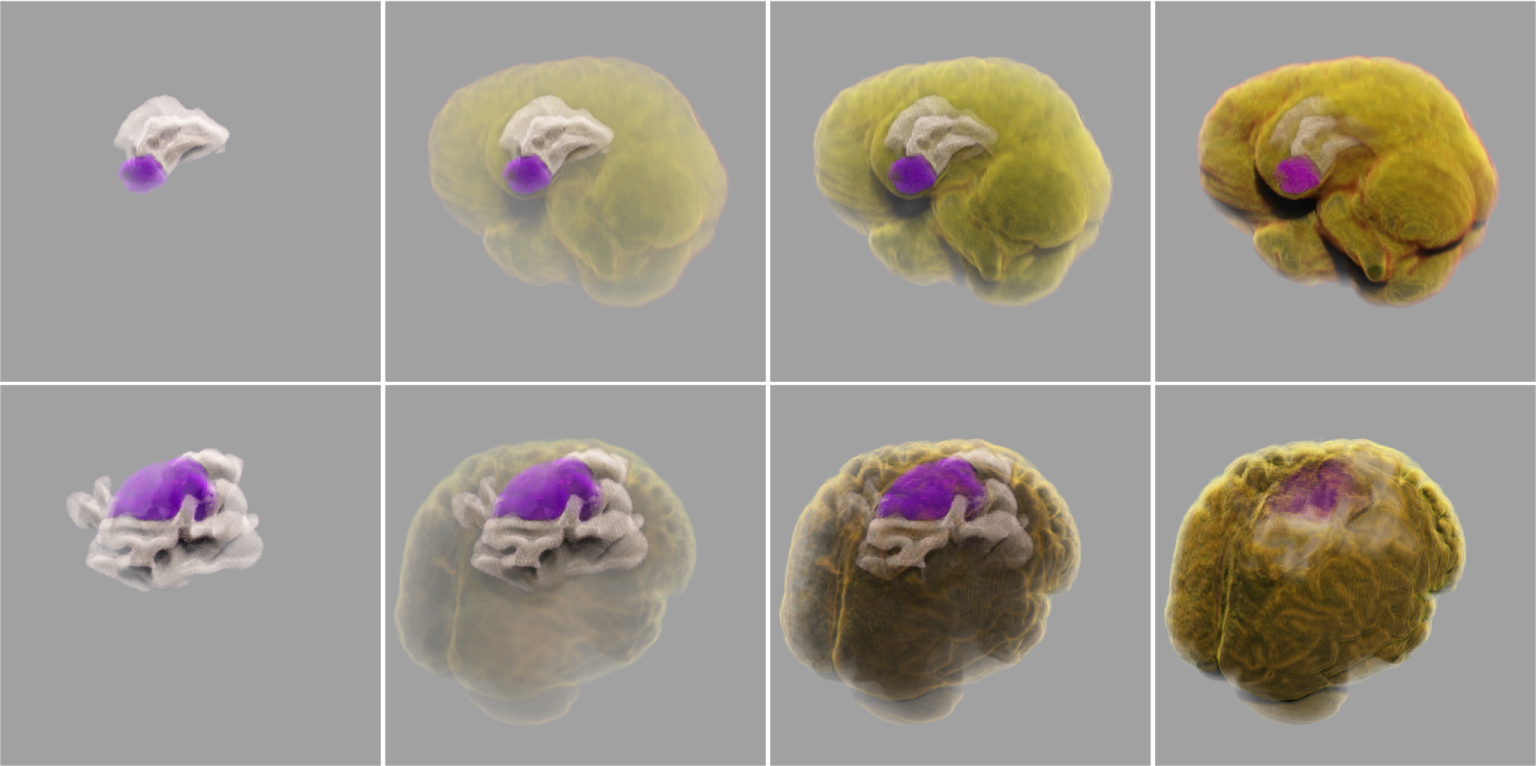

Semantic segmentation techniques are used to extract features of lesions or regions of interest and assign different material properties to them in rendering.

Brain tumors and tissue edema

Visualization without segmentation & Visualization with segmentation